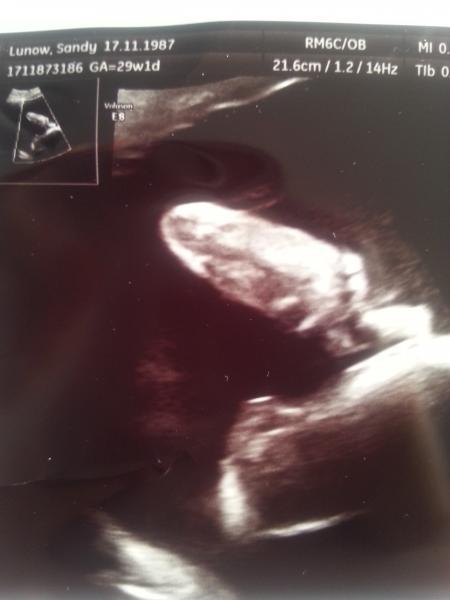

Alles super die kleine wieg 1.3kg und ihr ca end gewicht zu geburt sollte 3,3kg sein. Plazenta hat sich wie erhofft langer nach oben gezogen. Ihr Herz misst ca 4cm und bubert vor sich hin. wen ich zu Hause bin werd ich noch nen Bild hochladen. Sie war wie immer sehr Foto freutlich. ;)

Mmh, erkenne nix auf dem Bild! Aber schön, das alles ok ist. War ja auch heute beim 3. Screening, war auch alles bestens...